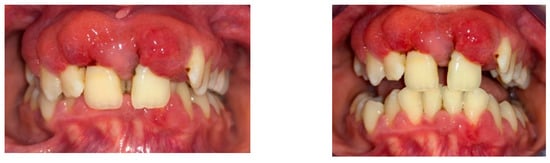

The initial radiography showed severe bone loss on the maxillary anterior tooth (Figure 3). In addition to the periodontal aspects, dental malposition of the maxillary and mandibular central and lateral incisors, deep bite malocclusion, deep hard palate, and advanced carious lesion in both maxillary first molars were observed. It was also not possible to specify whether the bone resorption in the anterior area was related to the trauma, considering that after the trauma, the patient did not request dental treatment.

Figure 3.

Initial panoramic radiograph.